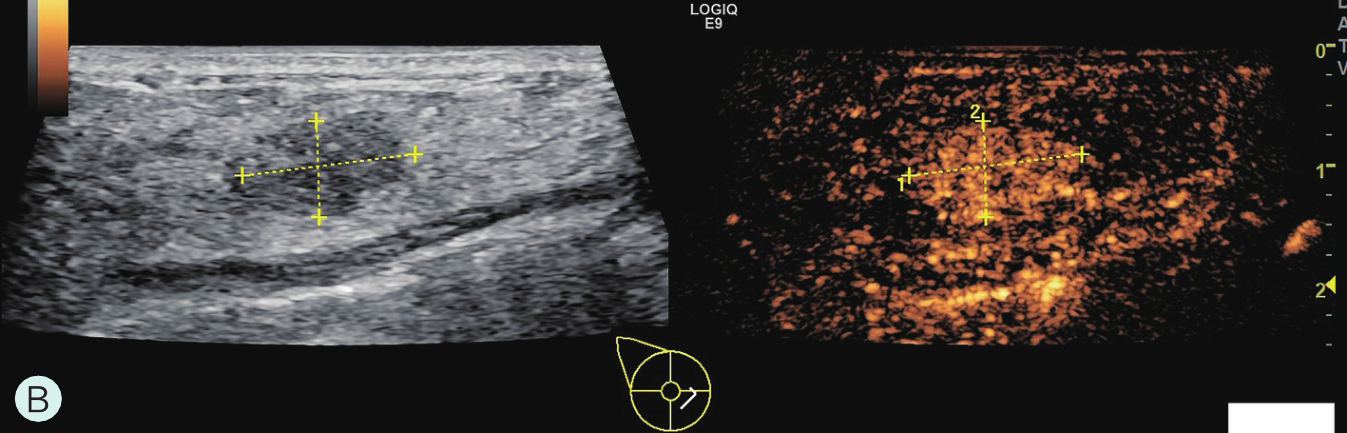

A.同步测量病灶大小与高增强范围;B.勾勒病灶与增强范围;C.定量分析